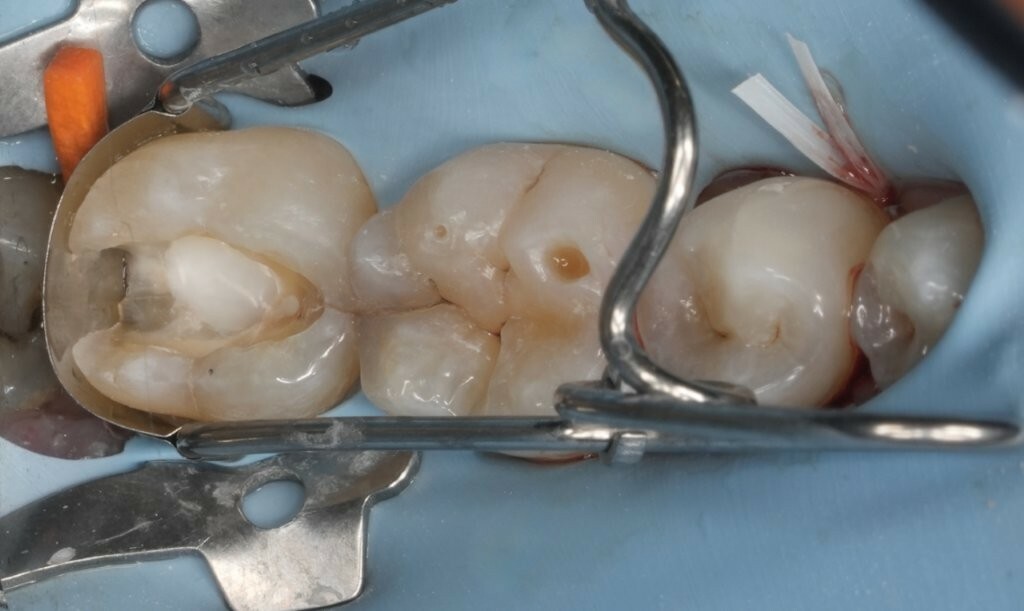

Abbildung 3: Direkte Überkappung der eröffneten Pulpa an Zahn 37 mit MTA vpt am zentralen Kavitätenboden.

Abbildung 4: Präzise Platzierung von GrandioSO Heavy Flow (Farbe WO) zur Versiegelung von MTA vpt unmittelbar nach der Applikation.